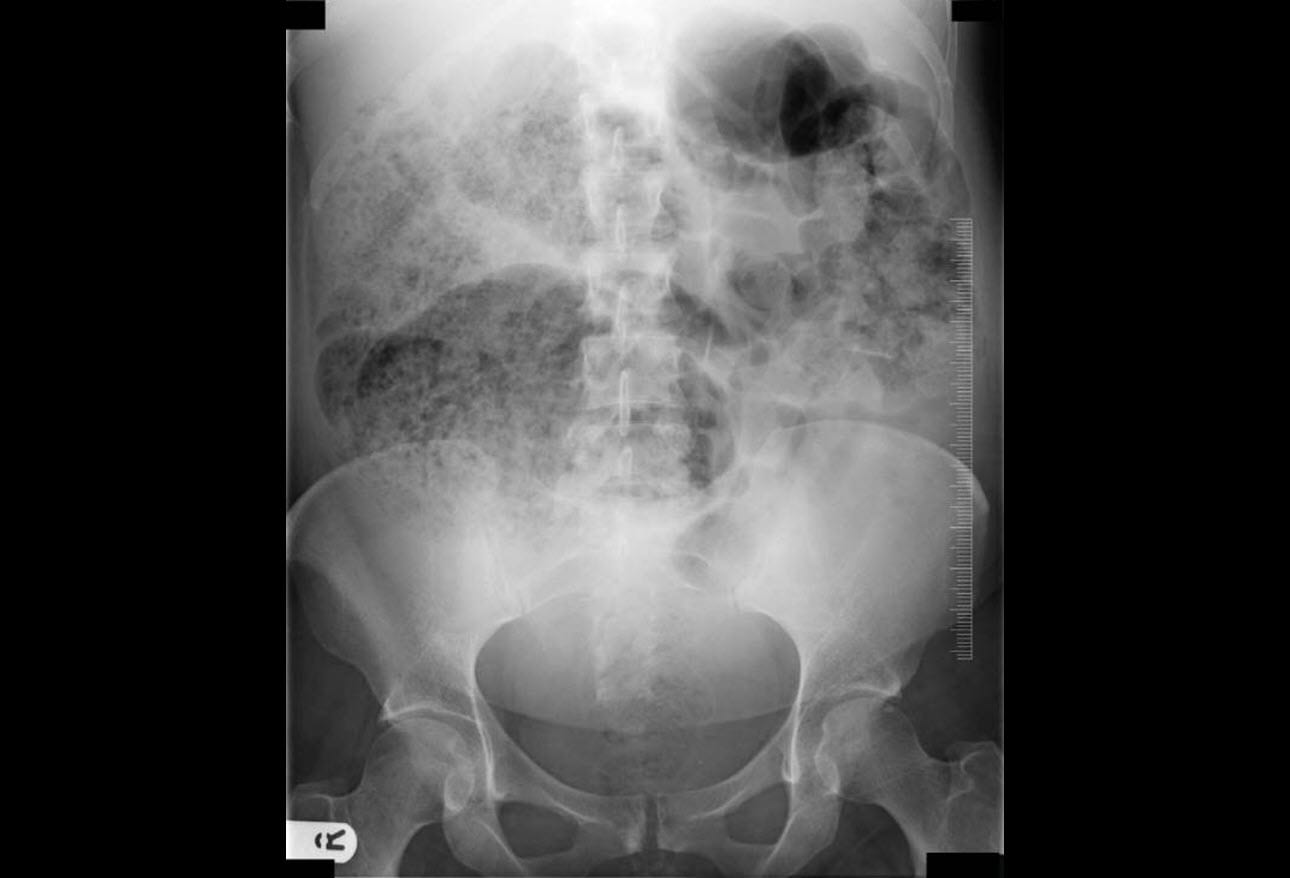

From ibimapublishing.com

The Giant Caecum with No Apparent Reason Ogilvie’s Syndrome Ogilvie Syndrome Symptoms Usually the patient has abdominal distention, pain and altered bowel movements. what are the symptoms of megacolon? In some cases the small bowel. learn about the definition, causes, symptoms, diagnosis, treatment, and outlook of intestinal pseudo obstruction, also. ogilvie syndrome is a rare disorder of colonic dilation and dysfunction that mimics mechanical obstruction. [2][8] there may also. Ogilvie Syndrome Symptoms.